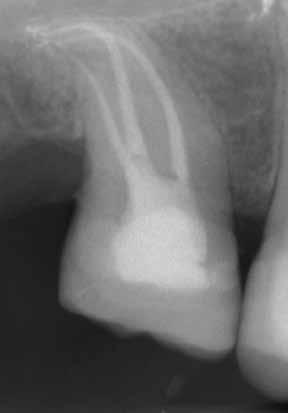

Due to the controlled memory, the files always follow the anatomy of the canal, thus significantly reducing the risk of ledging, transportation or perforation of a canal. Like stainless steel files, the HyFlex EDM files can be pre-bent.

This is a crucial advantage in extremely curved root canals to avoid the creation of steps.

Dr. Richard Gray

Dr. Byron Tsivos